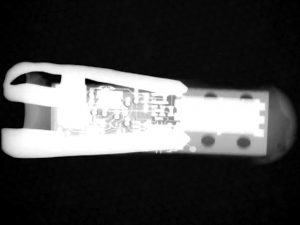

معلوم أنه بات بإمكان البشر هضم أنواع معيَّنة من الإلكترونيات التي تكون داخل كبسولات، ويتم إدخالها في الجسم عبر الأمعاء، لالتقاط صور الفديو وضخ الأدوية وتسجيل درجة الحرارة والحموضة، وغيرها من المؤشرات الصحية الحيوية. غير أن معظم هذه الإلكترونيات يعتمد على بطاريات تقليدية، تحتوي على مواد ضارة.لكن دراسة جديدة في كلية الطب في جامعة هارفارد، نشرت في مجلة “نايتشر بيوميديكال إنجينيريغ”، أظهرت أن هناك إمكانية لشحن هذه الإلكترونيات بواسطة تفاعل السوائل الكيميائية داخل الأمعاء، حيث يصبح بإمكانها العمل لعدة أيام دون الحاجة لأي مواد صناعية أخرى. وقال جيوفاني ترافيرسو أحد الباحثين في هذا المشروع: “لقد أثبت نموذجنا أنه بالإمكان حصاد الطاقة مدة أسبوع بهذه الطريقة”.

وتعتمد “الخلية الغلفانية” التي طوّرها العلماء لحصد الطاقة، على سوائل الأمعاء كجسر من المحلول الكهربائي بين القطب الزنكي الموجب والقطب النحاسي السالب. وعند تحلّل الزنك تتولَّد طاقة بمعدل 0.23 مايكرواط في كل ملليمتر مربع من القطب الموجب.

وفي إحدى التجارب، لاحظ العلماء أن باستطاعة إحدى الكبسولات المجهزة بهذه التقنية، استخدام جهاز إرسال بتردد 900 ميغاهيرتز لنقل حزم بيانات درجات الحرارة، بمعدل مرة كل 12 ثانية، إلى محطة أساسية تبعد مترين. وأظهرت تجربة أخرى أن إحدى الكبسولات استطاعــت بهذة الطاقــة المتولدة، جعل غشاء الذهب يتآكل كهربائياً ليفرج عن الأدوية إلى الأمعاء.

والأجهزة النموذجية الحالية هي إسطوانات بطول 40 ملليمتراً، وقطر 12 ملليمتراً، لكن العلماء يقولون إنَّه بالإمكان ترقية هذا الجهاز ليصبح أصغر حجماً.

ويلاحظ “ترافيرسو” أنه وزملاؤه طوروا حديثاً أجهزة بإمكانها البقاء في الأمعاء لأسابيع. وهي على شكل نجمي يمنعها من الانتقال والوصول إلى المعدة، في حين أن أذرعها رقيقة بما يكفي لكيلا تتسبب بأي انسدادات ضارة.